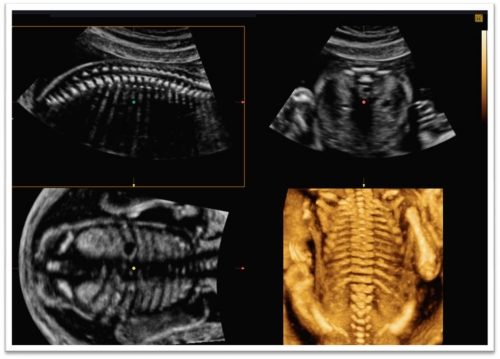

三维/四维超声作为临床超声诊断新技术,经过不断改进更新,使图像清晰、立体、逼真,提供的三维空间信息可弥补二维超声的不足,使超声诊断准确率明显提高。而实时三维超声能够清晰显示胎儿在宫内的各种姿势和动作, 如胎儿的手势、吞咽、打哈欠、 肢体运动等,图像质量不受胎儿运动的影响。

四维(实时三维)超声是在三维超声的基础上加上时间要素,从而展现动态连续的观察过程。三维超声成像的进一步发展体现在能够迅速地对容积图像数据进行储存、处理和显示其三维立体图像,并且能够得到多平面的图像,而这一切以往只有CT和MRI技术才具备。

目前三维超声尚不能取代二维超声,但它的确为一些复杂结构的判断提供大量的辅助信息,并对某些病变的诊断起到二维超声无法替代的作用,三维超声的应用正随着经验的积累发挥越来越大的作用。实时三维超声的出现极大提高了医生对先天性疾病诊断的信心,唇裂、脊柱形状异常,骨骼发育异常等的显示更为直观,易于理解。四维超声能够准确评估胎儿的睡眠与觉醒,为评估胎儿的生命状态提供了新的手段,准父母不经任何培训即可理解胎儿在宫内的姿势及动作,增进了亲子感情。